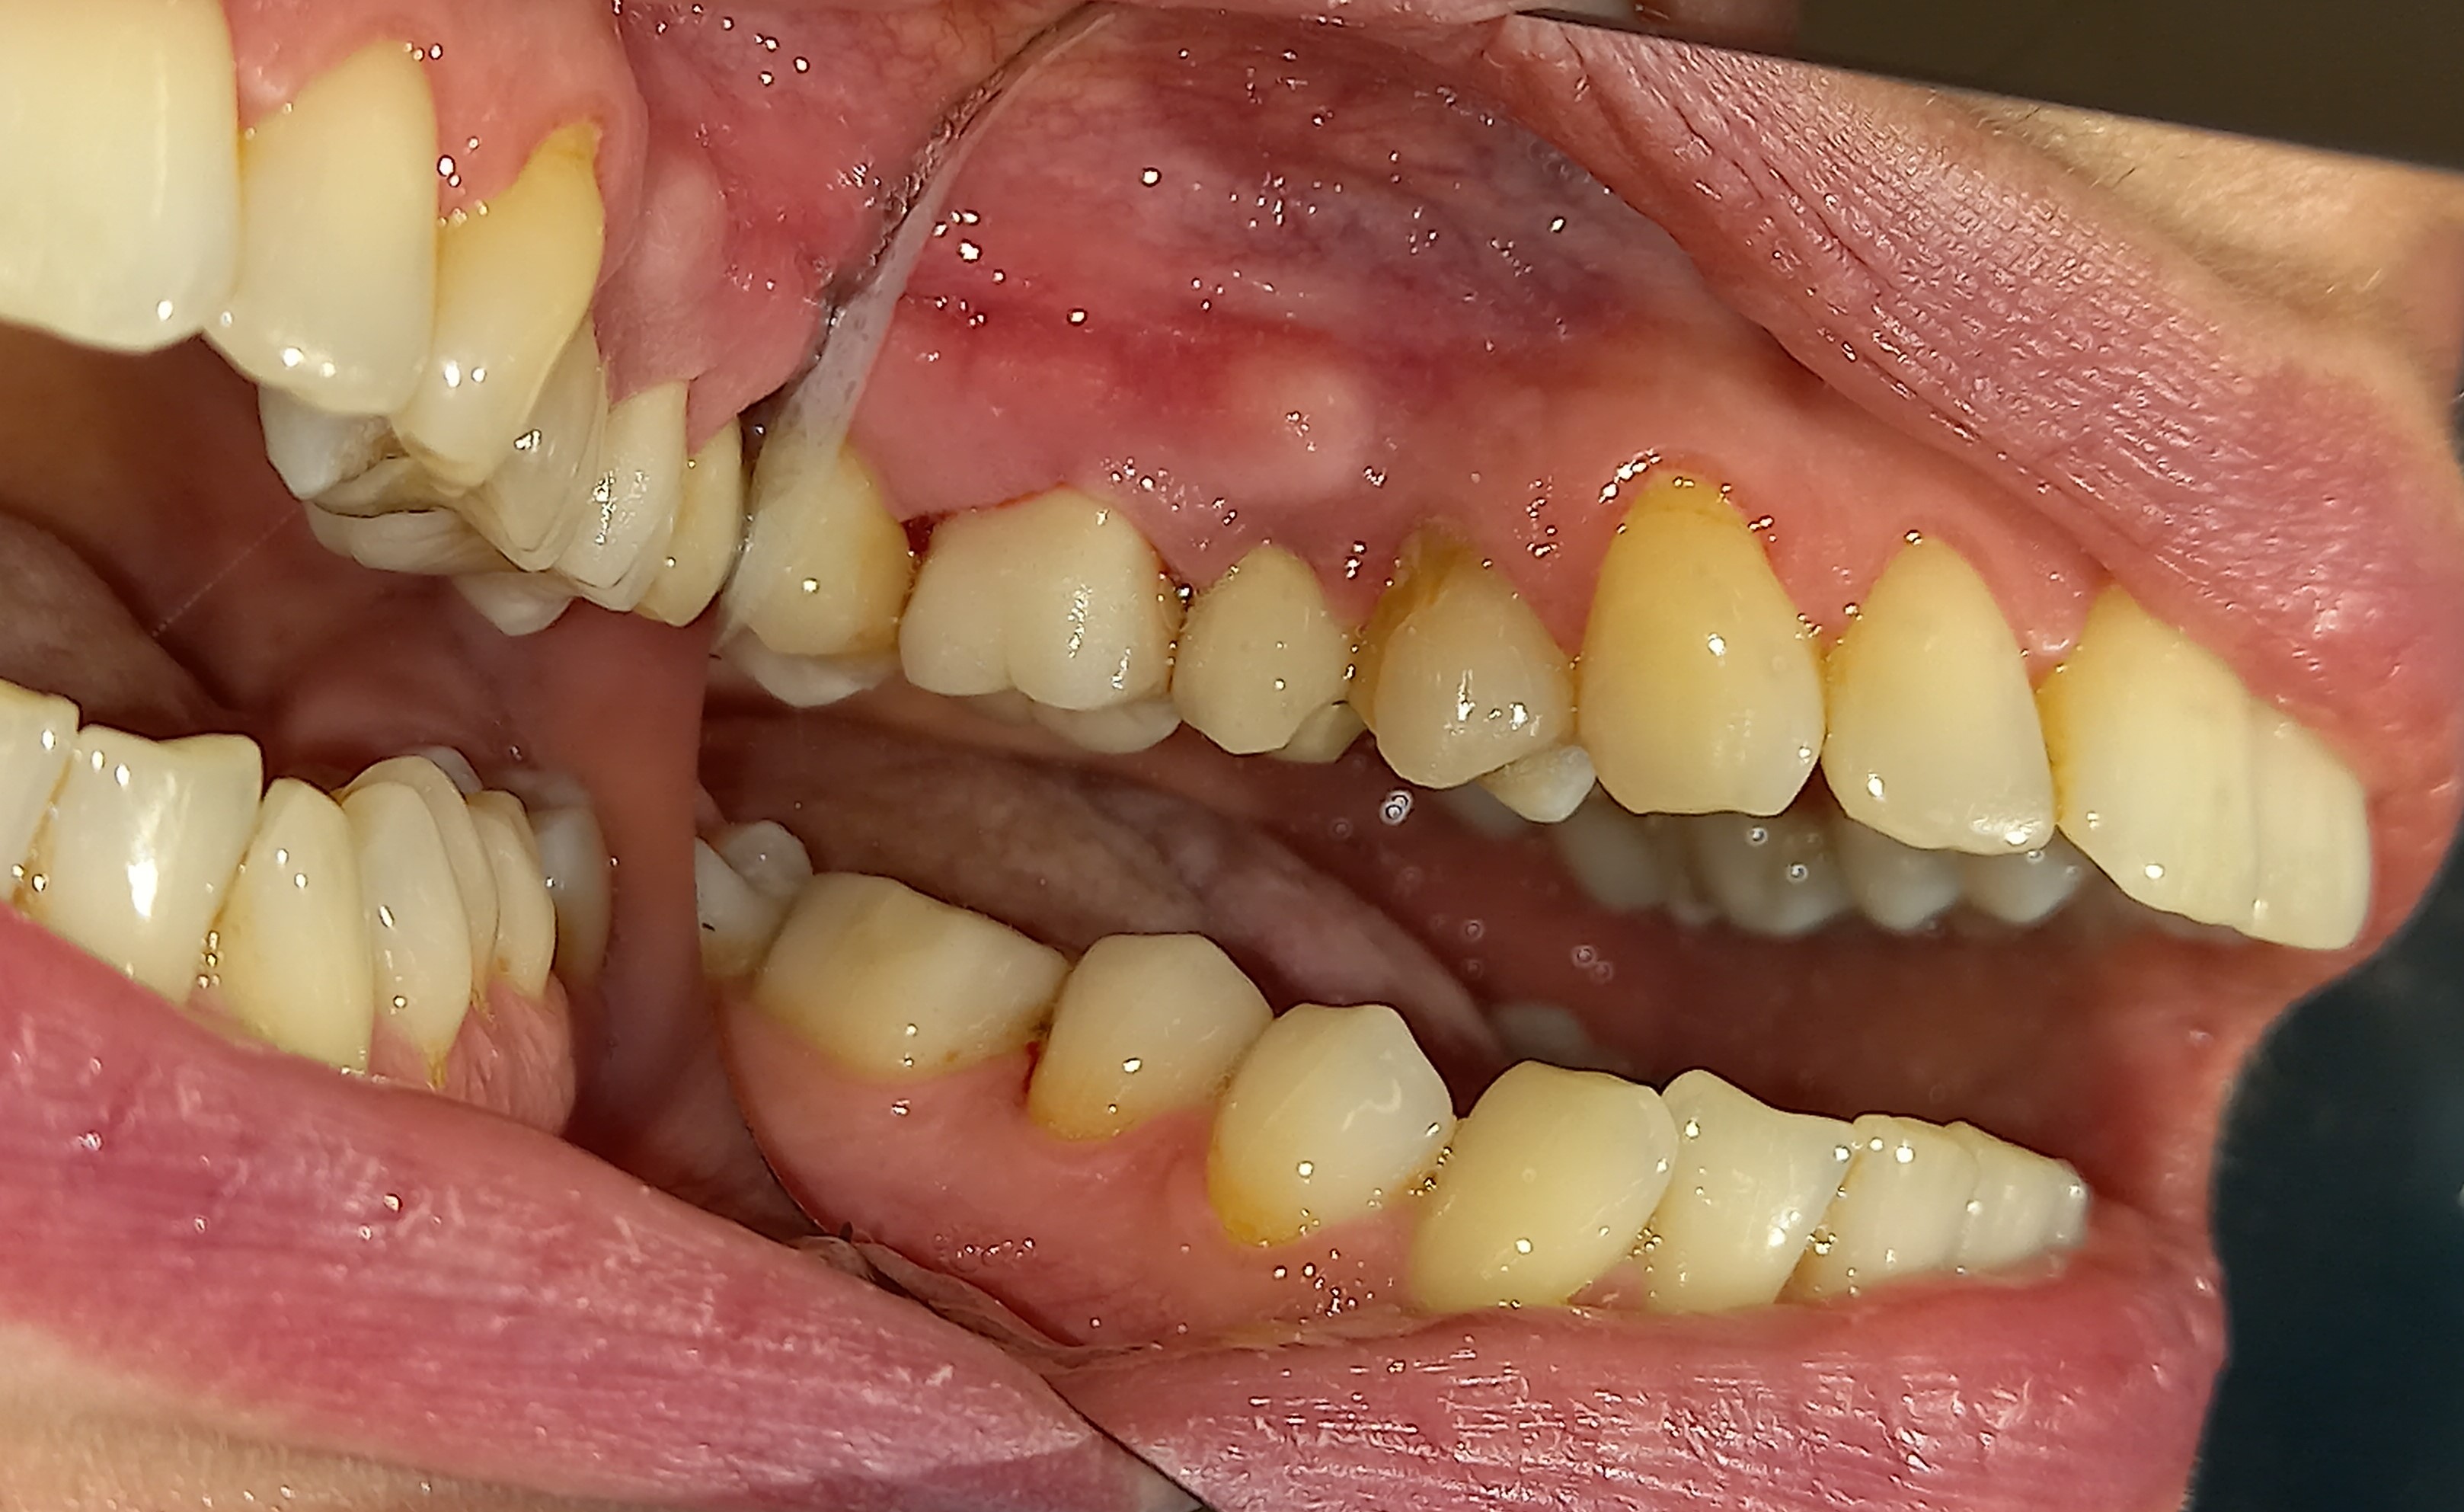

Ο ασθενής προσήλθε πρησμένος στην αριστερή πλευρά της κάτω γνάθου. Το πρόβλημα αφορούσε δύο γομφίους, από τους οποίους ο ένας ήταν ήδη απονευρωμένος και ο άλλος είχε βαθύ σφράγισμα, το οποίο έφτανε στο ύψος του νεύρου του δοντιού. Μετά την κλινική και ακτινογραφική εξέταση του δοντιού αποφασίστηκε η απονεύρωση του ενός γομφίου και η επανάληψη απονεύρωσης του άλλου γομφίου. Στο τέλος τα δύο δόντια θα προστατευτούν με θήκες δοντιών, εφόσον τα οδοντικά ελλείμματα ήταν μεγάλα.

Αρχική κλινική εικόνα του ήδη απονευρωμένου πρώτου γομφίου

Οι δύο γομφίοι μετά την ανασύστασή τους

Τελική εικόνα των δύο θηκών στους γομφίους